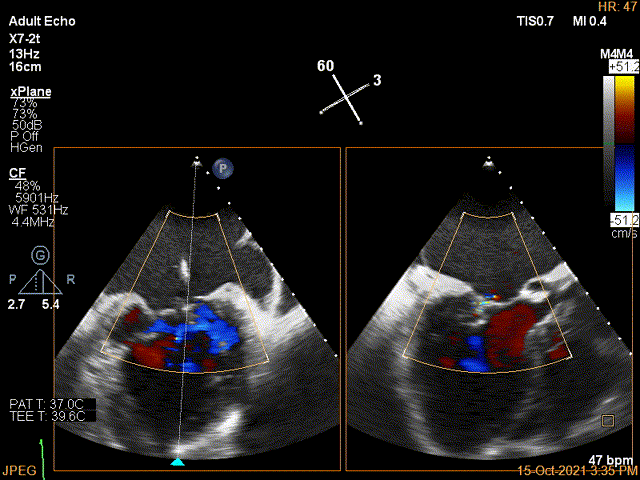

3D-color证实残余分流主要位于内侧2区

第一个夹子放置后二尖瓣口平均跨瓣压差:4mmHg

Color第二个夹子内侧残余小束分流,宽2.3mm

第二个夹子放置后二尖瓣口平均跨瓣压差:4mmHg